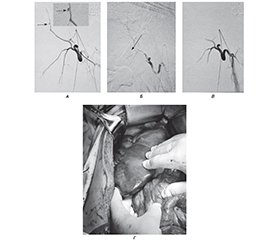

Мета: демонстрація можливостей застосування різних методів зупинки кровотечі з печінки внаслідок вогнепального торакоабдомінального поранення. Матеріали та методи. Пацієнт Х., 25 років, отримав поранення у груди під час мінометного обстрілу, доставлений через годину після поранення до передової хірургічної групи в тяжкому стані, виконаний торакоцентез справа, дренування плевральної порожнини за Бюлау, первинна хірургічна обробка (ПХО) ран. Через 2 години був доставлений до Військово-медичного клінічного центру Північного регіону КМС ЗСУ, госпіталізований до відділення невідкладної медичної допомоги. Встановлено діагноз: поєднане вогнепальне осколкове поранення грудей, живота, кінцівок. Сліпе торакоабдомінальне поранення справа з уламковим переломом VIII ребра, ушкодженням нижньої частки правої легені, правої частки печінки, правої нирки, з наявністю стороннього тіла (металевого осколка) в заочеревинному просторі. Правобічний гемопневмоторакс, пульмоніт. Гемоперитонеум. Сліпе поранення м’яких тканин правого плеча з наявністю стороннього тіла (металевого осколка). Операції: торакоцентез, дренування правої плевральної порожнини за Бюлау. ПХО вогнепальних ран. Пацієнт був оглянутий, виконували лабораторні дослідження: загальноклінічні аналізи крові, сечі, біохімічний аналіз крові, коагулограма крові, група крові та Rh-фактор, тромбоеластографія, електроліти крові, лужно-основний склад та гази крові, ультразвукове дослідження органів грудної клітки (ОГК) та органів черевної порожнини (ОЧП) за FAST-протоколом, мультиспіральна комп’ютерна томографія голови, ОГК та ОЧП і таза з контрастуванням та без контрастування, рентгенографічні дослідження голови, ОГК та ОЧП, електрокардіографія, ангіографічна діагностика та остаточна зупинка кровотечі, видалення стороннього тіла за допомогою інструмента магнітного багатофункціонального для діагностики і видалення металевих феромагнітних сторонніх тіл. Гемостаз рани печінки досягався за допомогою прошивання рани печінки, прийому Прінгла, тампонування серветками, застосування високочастотного електрохірургічного апарата Bowa ARC 303, ізольованого вихідного електрохірургічного генератора Valleylabtm LS10 та Medtronic AEXtm generator Aquamantys. Виконувались оперативні втручання за тактикою damage control surgery. Результати. При надходженні на УЗД грудей та живота за FAST-протоколом: наявна рідина в правій плевральній порожнині та черевній порожнині. При надходженні виконано МСКТ голови, ОГК, ОЧП і таза, виявлено вогнепальний перелом VIIІ ребра справа, посттравматичний пульмоніт нижньої частки правої легені, ознаки ушкодження Sg6, Sg7, Sg8 печінки, марлева серветка в печінці, стороннє тіло (металевий осколок) в ділянці верхнього полюса правої нирки, наявний дренаж у плевральній порожнині, ознаки малого гемопневмотораксу, ознаки гемоперитонеуму. На першу добу через 3 години після поранення виконано операцію DCS I. Лапаротомія, ревізія органів черевної порожнини та позаочеревинного простору справа. Атипова резекція Sg6, Sg7, Sg8 печінки. Ушивання та гемостаз печінки. Ушивання правого купола діафрагми. Видалення стороннього тіла (металевого осколка) за допомогою інструмента магнітного багатофункціонального для діагностики і видалення металевих феромагнітних сторонніх тіл. Тампонування печінки за типом «сендвіч». Ушивання верхнього полюса правої нирки. Санація та дренування черевної порожнини. Закрита лапаростома. Ревізія органів черевної порожнини, гемостаз та ушивання печінки, тампонування печінки за типом «сендвіч», санація та редренування черевної порожнини. Закрита лапаростома. Встановлено діагноз: поєднане вогнепальне осколкове поранення грудей, живота, кінцівок. Сліпе торакоабдомінальне поранення справа з уламковим переломом VIII ребра, ушкодженням нижньої частки правої легені, правої частки печінки (AAST IV), правої нирки (AAST III), з наявністю стороннього тіла (металевого осколка) в заочеревинному просторі. Правобічний гемопневмоторакс, пульмоніт. Гемоперитонеум. Сліпе поранення м’яких тканин правого плеча з наявністю стороннього тіла (металевого осколка). Операція: торакоцентез, дренування правої плевральної порожнини за Бюлау. ПХО вогнепальних ран. З’явились ознаки внутрішньочеревної кровотечі наступної доби з видаленням крові по дренажу з черевної порожнини. Виконано МСКТ голови, органів грудної клітки, органів черевної порожнини і таза з контрастуванням. За даними МСКТ голови, ОГК та ОЧП, таза з контрастуванням виявлені ознаки екстравазації контрастної речовини в черевну порожнину. Наступної доби у зв’язку з наявністю внутрішньочеревної кровотечі з печінки виконані re-look, ревізія органів черевної порожнини, гемостаз та ретампонування печінки, санація, редренування черевної порожнини, лапаростома. Через 12 годин після re-look рецидив внутрішньочеревної кровотечі. Виконана операція: ревізія органів черевної порожнини, гемостаз та ретампонування печінки, санація, редренування черевної порожнини, лапаростома. Через добу після поранення у зв’язку з рецидивом внутрішньочеревної кровотечі з печінки виконана ендоваскулярна емболізація гілок правої печінкової артерії. Виконана діагностична ангіографія судин печінки, під час якої виявлено джерело кровотечі у вигляді псевдоаневризми з однієї з гілок правої печінкової артерії. Права печінкова артерія відходить від верхньої брижової артерії. Виконана суперселективна катетеризація ушкодженої гілки правої печінкової артерії та її емболізація. Гемостаз досягнутий. Через 2 доби після поранення виконані re-look, ревізія органів черевної порожнини, детампонування печінки, санація, редренування черевної порожнини, закрита лапаростома. Через 4 доби після поранення виконано реторакоцентез зліва, дренування плевральної порожнини за Бюлау у зв’язку зі збільшенням кількості рідини в плевральній порожнині. На 5-ту добу після поранення пацієнт переведений на наступний рівень надання медичної допомоги. Відомо, що надалі на 10-ту добу була виконана атипова ререзекція печінки з закриттям лапаростоми та випискою пацієнта на 21-шу добу з представленням на військово-лікарську комісію і наданням відпустки за станом здоров’я на 30 календарних діб. Висновки. У наведеному клінічному випадку проведення ендоваскулярного гемостазу в комплексному лікуванні вогнепального поранення печінки, ускладненого абдомінальною кровотечею, із застосуванням тактики damage control surgery на фоні анатомічних особливостей відходження правої печінкової артерії показало свою високу ефективність.

Background. The goal is to demonstrate the possibilities of using various methods to stop bleeding from the liver due to a thoracoabdominal gunshot wound. Materials and methods. Male patient aged 25 years was wounded in the chest during mortar shelling. An hour after the wound, he was taken to the advanced surgical group in serious condition, and the right thoracocentesis, drainage of the pleural cavity according to Blau, and primary surgical treatment (PST) of the wounds were performed. After 2 hours, the patient was taken to the Military Medical Clinical Center of the Northern Region of the Military Medical Service of the Armed Forces of Ukraine, and hospitalized in the emergency department. The diagnosis was: combined gunshot shrapnel wound of the chest, abdomen, and extremities. Blind thoracoabdominal wound on the right with a comminuted fracture of the VIII rib, damage to the lower lobe of the right lung, right lobe of the liver, right kidney with the presence of a foreign body (metal fragment) in the retroperitoneal space. Right-sided hemopneumothorax, pneumonitis. Hemoperitoneum. Blind wound of the soft tissues of the right shoulder and the presence of a foreign body (metal fragment). Operations: thoracocentesis, drainage of the right pleural cavity according to Blau. PST of gunshot wounds. The patient was examined, laboratory tests were performed: general clinical blood, urine tests, biochemical blood test, blood coagulogram, blood group and Rh factor, thromboelastography, blood electrolytes, alkaline-base composition and blood gases, ultrasound examination of the chest and abdominal organs according to the FAST protocol, multislice computed tomography (MSCT) of the head, chest, abdominal organs and pelvis with and without contrast, radiographic examinations of the head, chest and abdominal organs, electrocardiography, angiographic diagnosis and final stoppage of bleeding, removal of a foreign body using a multifunctional magnetic instrument for the diagnosis and removal of metallic ferromagnetic foreign bodies. Hemostasis from the liver wound was achieved by suturing the liver wound, Pringle maneuver, tamponade with gauze, using a Bowa ARC 303 high-frequency electrosurgical device, an isolated output electrosurgical generator Valleylab™ LS10, and a Medtronic AEX™ generator Aquamantys. Surgical interventions were performed using the (DCS) technique. Results. Upon admission, chest and abdominal ultrasound using the FAST protocol was done: fluid in the right pleural cavity and abdominal cavity. MSCT of the head, chest, abdominal organs and pelvis was also performed, which revealed a gunshot fracture of the right VIII rib, post-traumatic pneumonitis of the lower lobe of the right lung, signs of damage to Sg6, Sg7, Sg8 of the liver, gauge in the liver, foreign body (metal fragment) in the area of the upper pole of the right kidney, pleural drainage in the pleural cavity, signs of small hemopneumothorax, signs of hemoperitoneum. On the first day, 3 hours after the injury, DCS I was performed. Laparotomy, revision of the abdominal organs and the right extraperitoneal space. Atypical resection of Sg6, Sg7, Sg8 of the liver. Suturing and hemostasis of the liver. Suturing of the right dome of the diaphragm. Removal of a foreign body (metal fragment) using a multifunctional magnetic instrument for the diagnosis and removal of metal ferromagnetic foreign bodies. “Sandwich” liver tamponade. Suturing of the upper pole of the right kidney. Sanitation and drainage of the abdominal cavity. Closed laparostomy. Revision of the abdominal organs, hemostasis and suturing of the liver, “sandwich” liver tamponade, sanitation and re-drainage of the abdominal cavity. Closed laparostomy. The diagnosis was established: combined gunshot shrapnel wound of the chest, abdomen, and extremities. Blind thoracoabdominal wound on the right with a comminuted fracture of the VIII rib, damage to the lower lobe of the right lung, right lobe of the liver (AAST IV), right kidney (AAST III) with the presence of a foreign body (metal fragment) in the retroperitoneal space. Right-sided hemopneumothorax, pneumonitis. Hemoperitoneum. Blind wound of the soft tissues of the right shoulder and the presence of a foreign body (metal fragment). Operation: thoracocentesis, drainage of the right pleural cavity according to Blau. PST of gunshot wounds. Signs of intra-abdominal bleeding appeared the next day with blood being removed from the abdominal cavity through drainage. MSCT of the head, chest, abdominal and pelvic organs with contrast was performed, signs of extravasation of contrast material into the abdominal cavity were detected. The next day, due to the presence of intra-abdominal bleeding from the liver, a re-look, revision of the abdominal organs, hemostasis and re-tamponade of the liver, sanitation, re-drainage of the abdominal cavity, and laparostomy were performed. Twelve hours after a re-look, intra-abdominal bleeding relapsed. The operation was performed: revision of the abdominal organs, hemostasis and re-tamponade of the liver, sanitation, re-drainage of the abdominal cavity, laparostomy. A day after the injury, endovascular embolization of the branches of the right hepatic artery was performed due to recurrence of intra-abdominal bleeding from the liver. Diagnostic angiography of the liver vessels was performed, during which the source of bleeding was identified as a pseudoaneurysm from one of the branches of the right hepatic artery. The right hepatic artery originates from the superior mesenteric artery. Superselective catheterization of the damaged branch of the right hepatic artery and its embolization were performed. Hemostasis was achieved. Two days after the injury, a re-look, revision of the abdominal organs, liver detamponade, sanitation, re-drainage of the abdominal cavity, and a closed laparostomy were performed. Four days after the injury, left re-thoracocentesis and drainage of the pleural cavity according to Blau were conducted due to an increase in the amount of fluid in the pleural cavity. On the fifth day after the injury, the patient was transferred to the next level of medical care. It is known that subsequently, on the 10th day, an atypical liver re-resection was performed with laparostomy closure, and the patient was discharged on the 21st day with presentation to the military medical commission and provision of sick leave for 30 calendar days. Conclusions. The presented clinical case of endovascular hemostasis in the comprehensive treatment of gunshot wounds of the liver complicated by abdominal bleeding using the damage control surgery against the background of anatomical features of the right hepatic artery origin showed its high effectiveness.